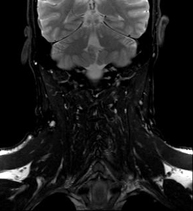

- Neck MRI

This non-invasive diagnostic procedure uses an electromagnetic field and radio waves (from a transmitter and receiver) to acquire high-definition anatomical images of the neck. It is a radiation-free procedure. Indicated for: suspected tumours, infections, lymph nodes.

This non-invasive diagnostic procedure uses an electromagnetic field and radio waves (from a transmitter and receiver) to acquire high-definition anatomical images of the neck. It is a radiation-free procedure. Sometimes paramagnetic contrast (gadolinium) must be used to complete the study.